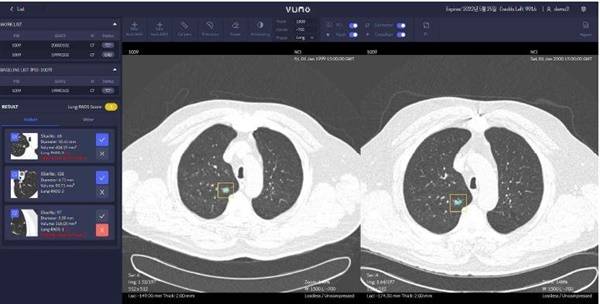

| ▲ 주식회사 뷰노의 흉부 CT 영상으로 폐결절 탐지에서 악성도 평가까지 가능한 기술로 미국 임상 검증 사례 |

| ⓒ 한국보건산업진흥원 제공 |

국제협력연구에서 ▲흉부 CT영상 활용 폐암 조기 진단 인공지능 소프트웨어 ▲소화기관 조기 암질환 대상 복부 최소침습 수술로봇 ▲혈중 내 바이오마커 활용 대장암 선별 체외진단 의료기기 ▲갑상선 기능이상 및 안병증 소프트웨어 의료기기 등 4건의 기술과 해외임상지원에서 ▲ 흉부 CT영상 활용 심폐질환 진단 인공지능 소프트웨어 1건이 그것이다.